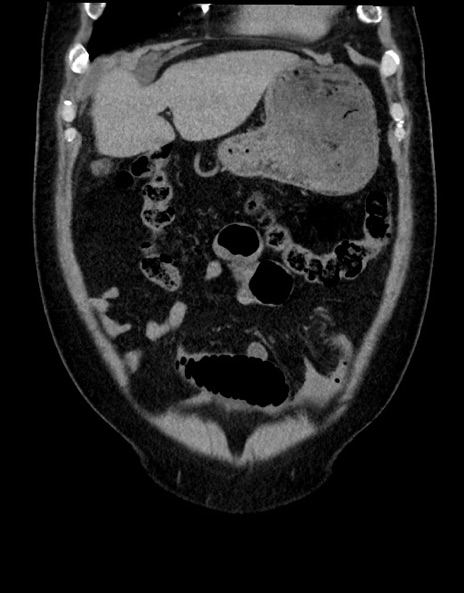

横断像

【症例】70歳代男性

【主訴】腹痛

【現病歴】今朝から腹痛あり。全体的に痛い。特に左上の方。排ガスが今日はない。冷や汗が出る。

【既往歴】直腸癌術後

【身体所見】左側腹部〜上腹部に圧痛あり。腹膜刺激症状明らかなではない。軽度反跳痛。左下腹部に術後瘢痕あり。

【データ】WBC 7700、CRP 0.02